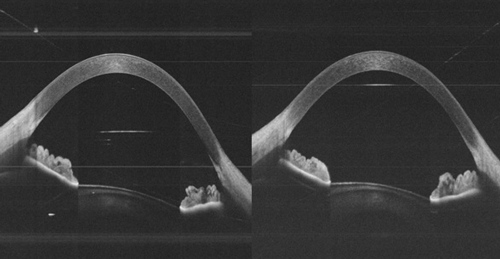

Figure 2: Binocular, simultaneous imaging allows automated, quantitative pupillometry using OCT (the images shown are from the binocular OCT prototype device currently undergoing clinical testing in Moorfields Eye Hospital).

Binocular OCT systems also allow real-time high-speed image capture from both eyes at the same time. This ‘simultaneous’ ocular imaging expands the range of functional testing possible. Pupillometry, for example, can offer valuable information regarding the presence of eye disease. The conventional method of testing pupils involves shining a pen torch into the eyes, and relies upon a trained examiner visualising pupil responses. In this way, pupillary defects are often subtle and easily missed, and many potential sources of error may confound the results, including anisocoria and off-axis pupil illumination. Using the binocular OCT, a controlled flash of light is presented to the user while the OCT dynamically captures images through the iris planes (Figure 2). By measuring the width of the pupil in rapidly acquired pairs of B-scans, pupil parameters such as maximum and minimum pupil diameter, velocity and amplitude can be quantitatively measured, and subtle pupillary defects can be detected.